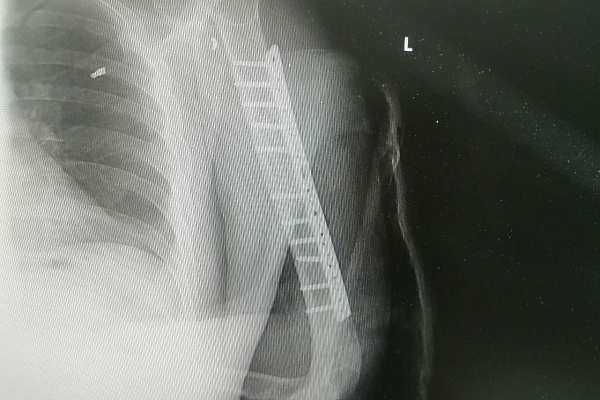

Травматологи-ортопеды Владимир Кельметр и Алексей Котов оперировали пациента более четырех часов. Целостность лучевого нерва они восстановили за счет фрагмента сурального нерва, который выделили из голени. Следующим этапом был остеосинтез плечевой кости. Её отломки соединили накостной пластиной, создав условия для скорейшей консолидации перелома.